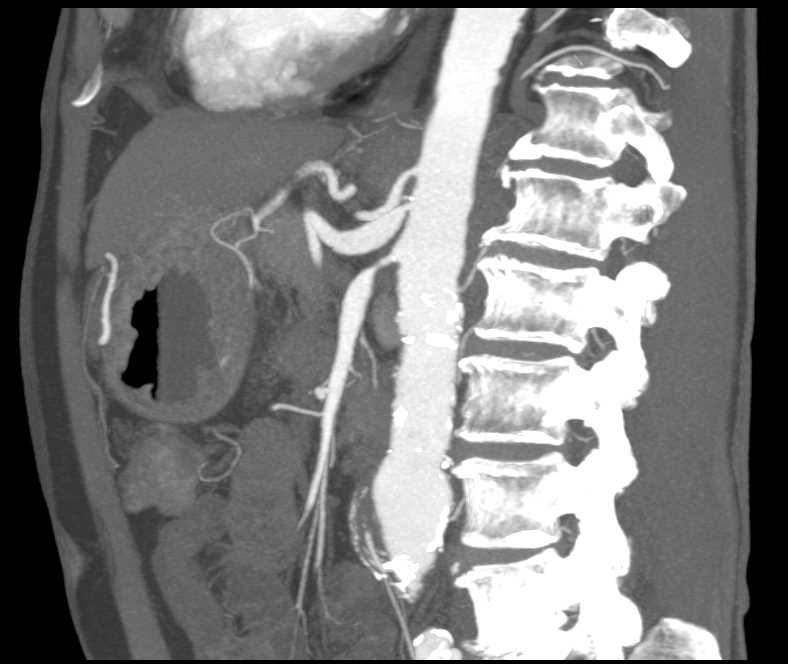

Calcified Right Adrenal Gland due to Prior Trauma